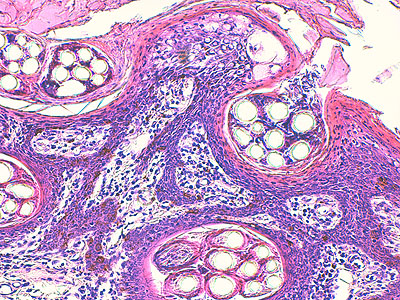

Photo 5 (Hémalun Eosine X 200) : ces crêtes épithéliales tout à fait particulières

(allongées, filiformes, branchues) peuvent également être présentes dans les couches les plus basales

de la gaine épithéliale folliculaire externe des infundibula folliculaires.

On note également l’aspect parakératosique diffus des infundibula folliculaires.

Légendes de la Photo 5 :

- Triangles bleus : contours de crêtes épithéliales allongées, filiformes, ramifiées et branchues, peuplées de cellules basales hyperbasophiles, émanant de la gaine épithéliale externe des infundibula folliculaires

- Flèches rouges : parakératose épidermique et folliculaire

- Étoiles rouge pleines : Le derme est faiblement à modérément inflammatoire (infiltrat mononucléé)

- Étoiles rouge claires : angiectasie des capillaires sanguins

- Ronds marrons : tiges pilaires